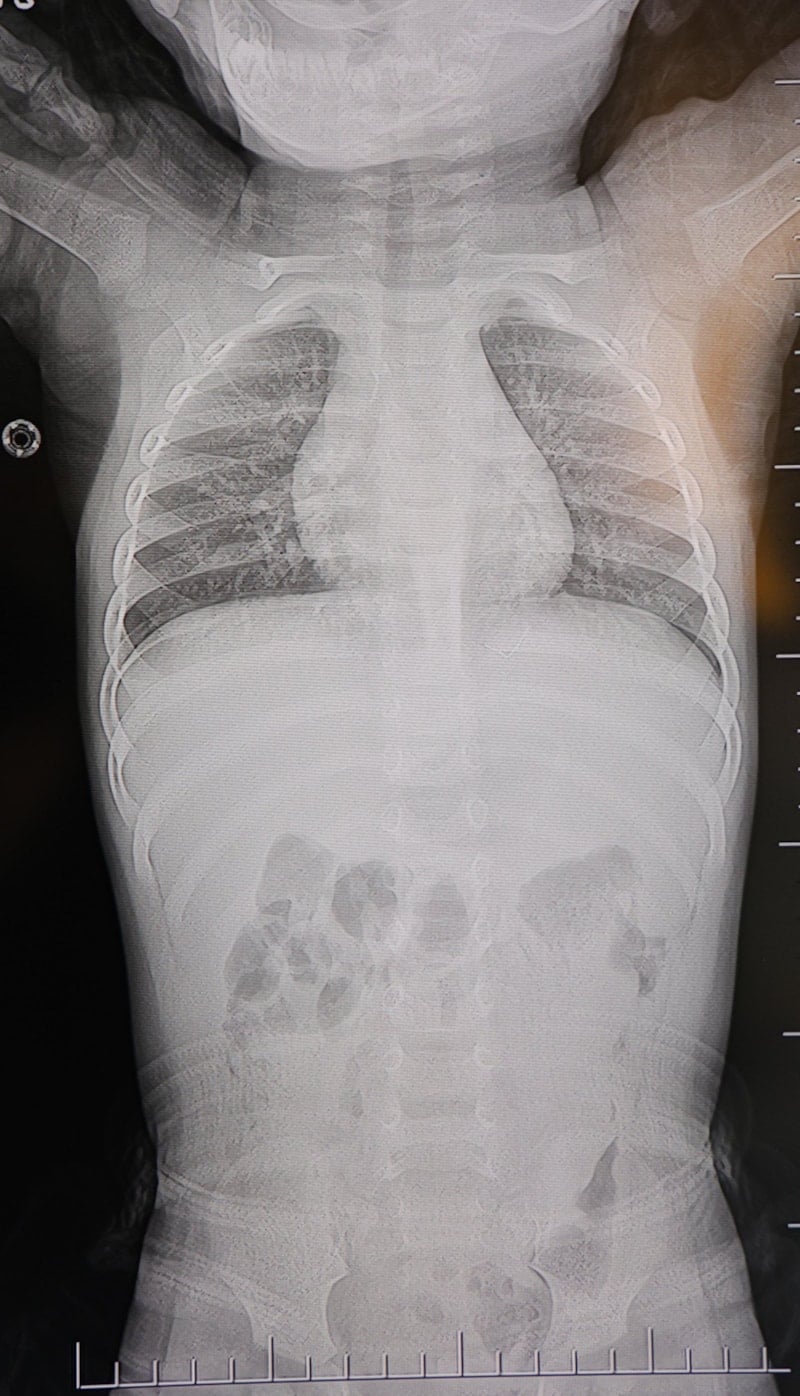

Baba Poyraz, bir gün acil serviste yapılan kontrollerde bebeğin belinde yabancı cisim olduğunu, çekilen filmlerde ise "L" şeklinde zımba teli tespit edildiğini söyledi.

Başhekim yardımcısının yönlendirmesiyle tomografi çekildi. O zaman belinde zımba teli olduğu netleşti. Başka bir hastaneye götürdük, 'riskli, 8 yaşına kadar alınamaz' dediler, geri gönderdiler. Eve geldikten üç gün sonra oğlum bayıldı. Kardeşimle özel hastaneye götürdük. Orada filmlere baktılar, 'akciğere doğru gidiyor, L şeklinde zımba teli var, alınması lazım' dediler." dedi.